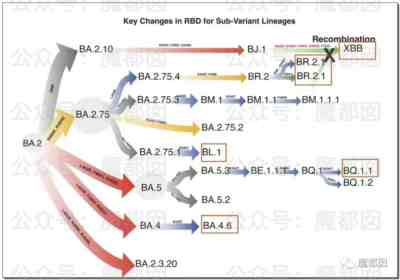

1、我们今天对付的是一种病毒吗?很多人可能会奇怪反问我们,难道不就是新冠一种吗?大错特错,如果严肃点说,我们现在面对的是几百种病毒,只不过这几百种病毒统称新冠,这几百种病毒里随随便便拿几个出来就足以让我们躺下。

我们举个例子,今天曾经热搜第一的XBB。

XBB是个什么水平?

换言之,我们周围把我们搞得半死不活的毒株其实都是“老版本”,目前中国疫情爆发的主要毒株是BA.5.2和BF.7,美国的毒株变异比国内毒株要快2代。至于XBB在中国日后会有什么发展,那完全不得而知了。很有可能以后会是那种“一锅大乱炖”的情形: